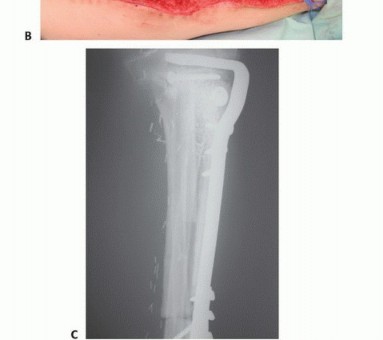

- الأشعة السينية العادية (Plain Radiography): تُظهر صور الأشعة السينية العادية (FIG 4AB) العيب العظمي وحجمه، وتساعد في تقييم بنية العظم المحيطة.

تصوير عيوب العظام

- أ. صورة شعاعية عادية للظنبوب تُظهر ساركوما عظمية كبيرة منخفضة الدرجة في الجزء الجذعي.

- ب. صورة شعاعية عادية للذراع تُظهر فقدانًا كبيرًا للعظم وكسرًا مرضيًا مرتبطًا بالتهاب العظم والنقي الحاد في جسم العضد.

- ج. إعادة بناء مقطعي محوسب إكليلي للساعد البعيد يُظهر ساركوما عظمية في الكعبرة البعيدة.